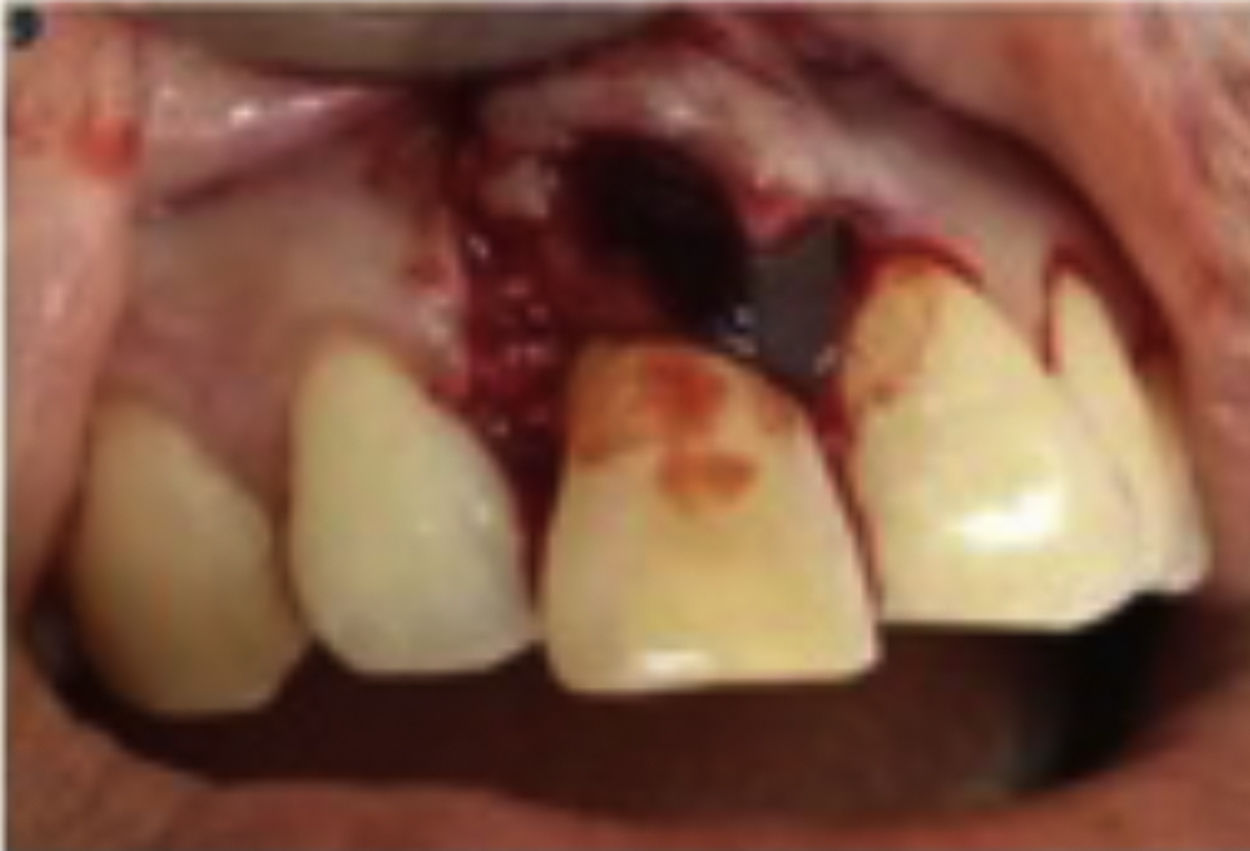

Bone graft was placed on a bone defect and PRF was placed on top of it (Figs. 8 and 9). Flap reposition was done with interrupted suture technique (Fig. 10). The periodontal dressing was placed as the final step (Fig. 11).

Postoperative instructions, amoxicillin 500mg, mefenamid acid, vitamin C and minocep rinse were prescribed. One week after the procedure, there was little erythema on the sutured area. There was no flap dehiscence or suppuration (Fig. 12a). Three months follow up after procedure showed significant improvement (Fig. 12b). Periapical radiography showed significant bone formation characterized by a decrease in radiolucency and hypercementosis area (Fig. 13).